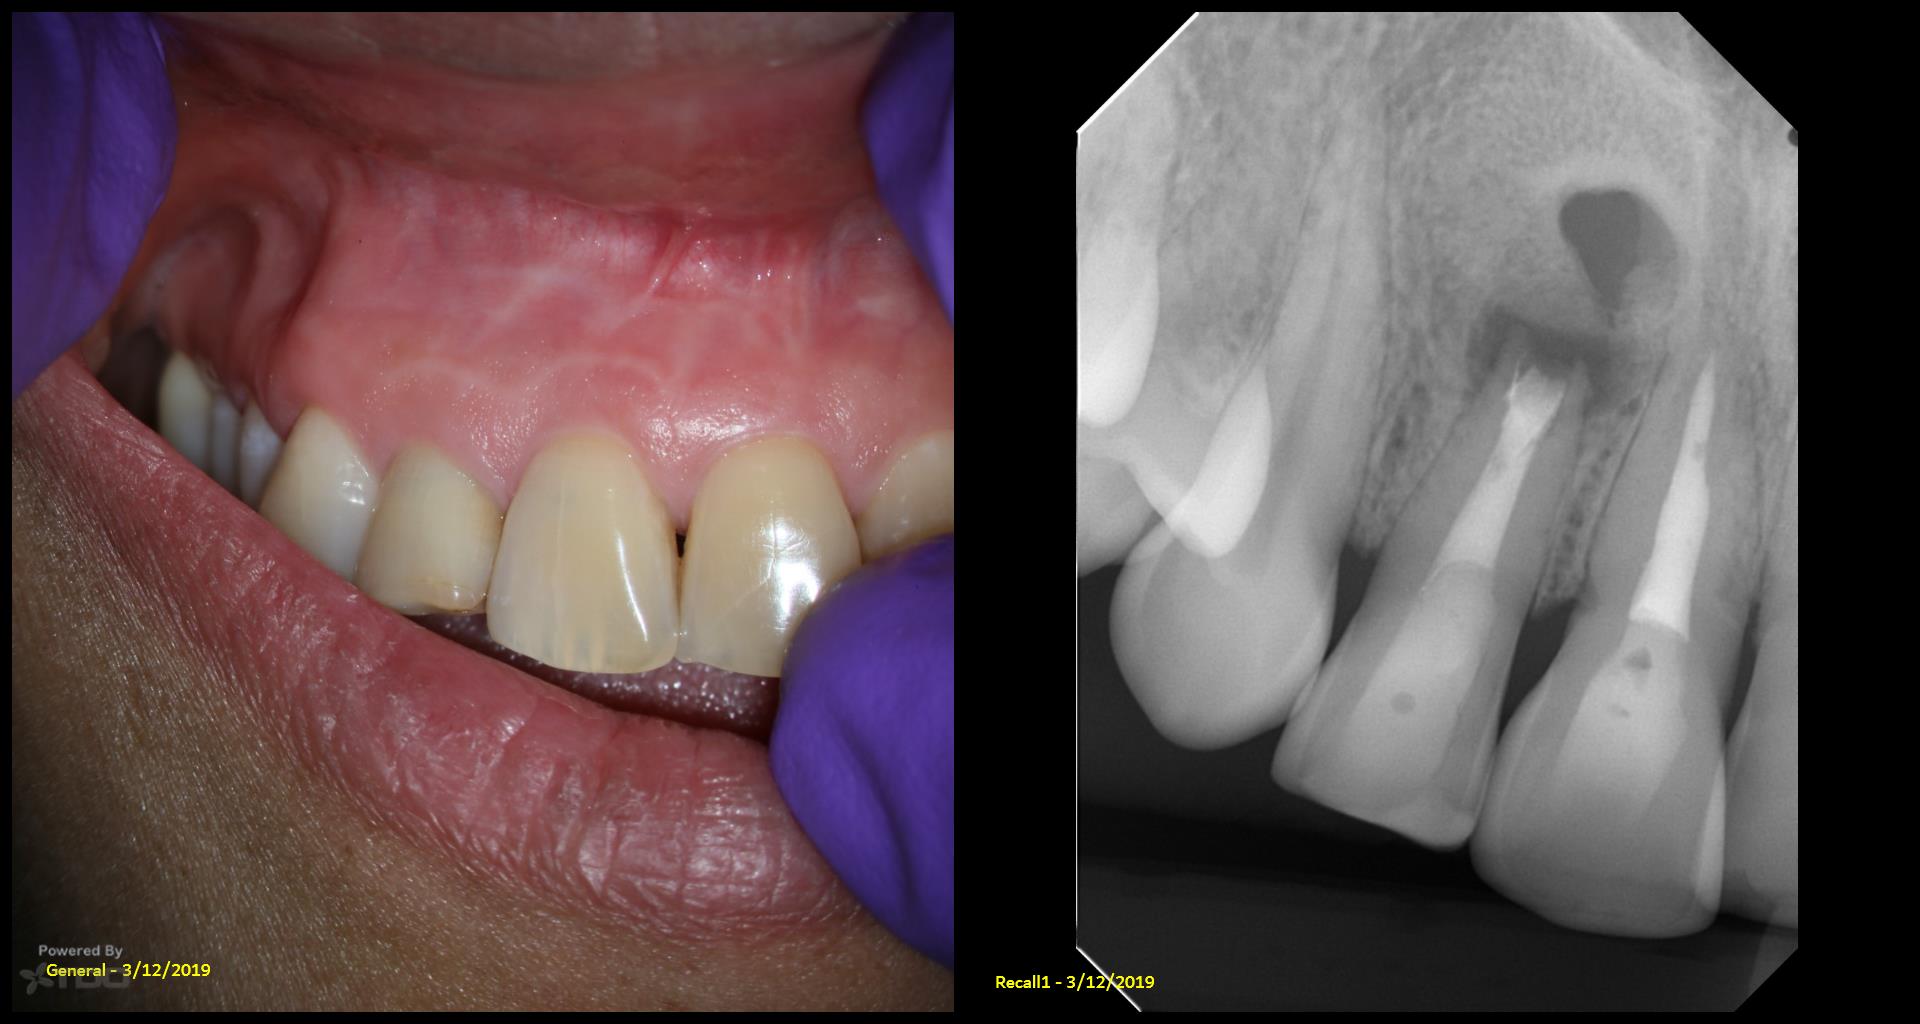

Do you have the previous review x ray s,